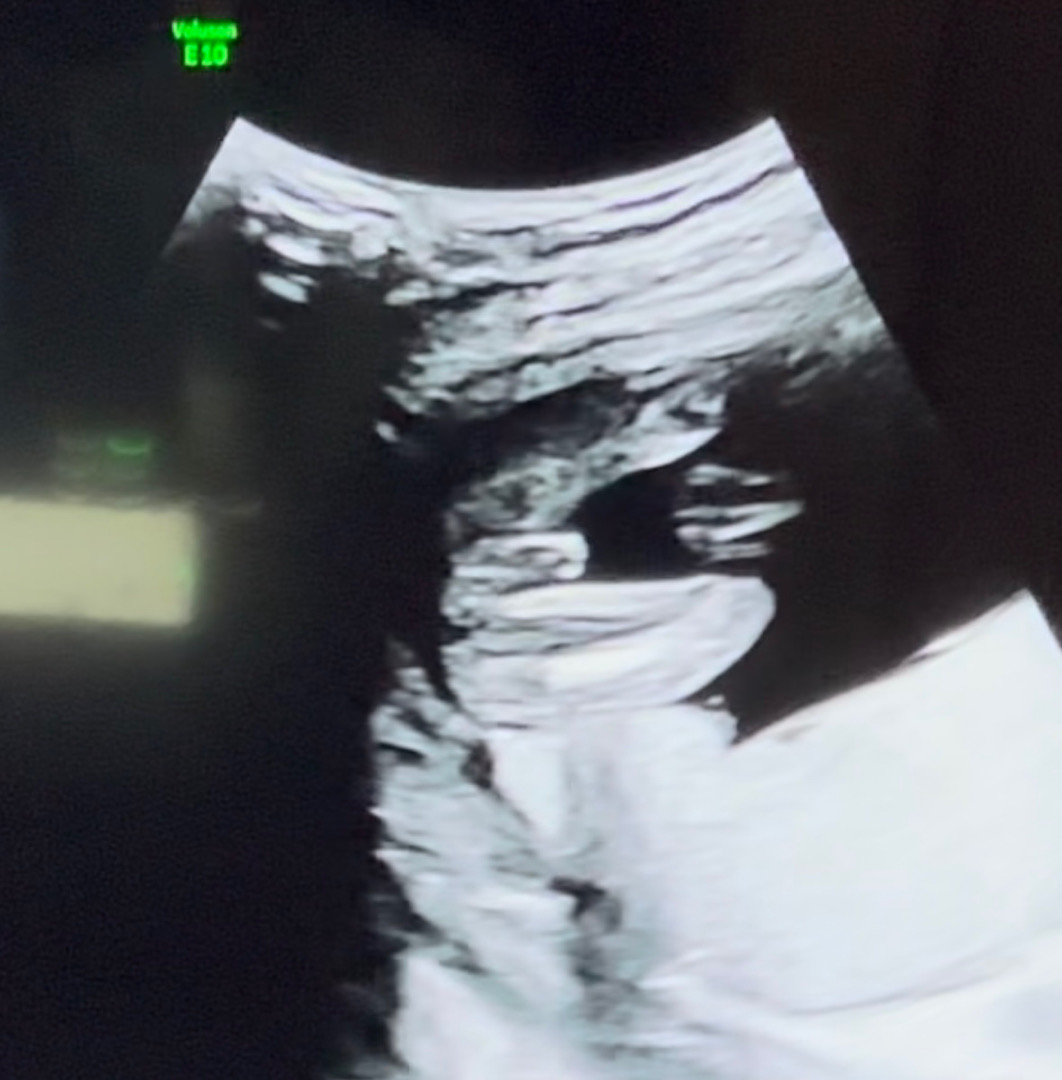

아들일까요???

선생님은 애기가 잘안보여주긴하는데 아들일가능성이 높을거같다고 하시더라구요 어떤가요 ㅍ3ㅍ